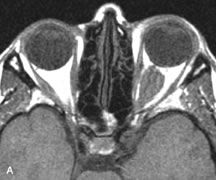

PATIENT PREPARATION Before MRI is performed, patients must be screened and prepared to avoid the potential hazards associated with the strong magnetic field. Patients who have ferrous aneurysm clips or cardiac pacemakers, who depend on life-support equipment, or who retain a possible metallic intraocular foreign body are not candidates for this imaging modality. MRI cannot be performed on obese patients who cannot fit into the bore of the magnet. Patients who are claustrophobic may not tolerate a prolonged period of study within the confines of the magnet, whereas others might do well if given a mild sedative. All worn metallic objects (e.g., necklaces, watches) should be taken off, credit cards set aside, and eye makeup removed before entering the room containing the magnet.5,20,34,35,36 NORMAL ORBITAL ANATOMY T1-weighted images provide the best anatomic details of the orbit because they display superior contrast resolution between normal structures (see Fig. 8). The vitreous has a long T1, resulting in an intermediate signal similar to brain, whereas the crystalline lens and sclera appear dark because of a longer T1 and short T2. The extraocular muscles, like all skeletal muscles, demonstrate a moderately long T1 and short T2 and highly contrast with the intense signal of the surrounding orbital fat (adipose tissue has an extremely short T1). The lacrimal glands appear as mottled areas of reduced intensity of the signal from the orbital fat in the lacrimal fossa. The optic nerves are seen with the same signal intensity as brain white matter and are hypointense relative to the orbital fat because their Tl is longer than the Tl of fat but shorter than the Tl of water. Cortical bone is not well delineated because it contains little free water, yielding minimal signal in MRI, and thus appears dark on all pulse sequences. This feature explains why MR images of the orbital apex and intracanalicular portion of the optic nerves are superior to comparable CT scans. Partial volume averaging of the bones in these regions obscures soft tissue details on CT images, whereas MRI reveals the signals only from the soft tissue structures with no cortical bone input. Bone marrow, on the other hand, is seen as a relatively intense signal because of its high fat content (see Fig. 8).37,38 T2-weighted pulse sequences are not ideal for imaging normal anatomy; however, they are particularly useful in revealing pathologic conditions (see Fig. 9). T2-weighted studies are most easily recognized by a bright vitreous signal. ORBITAL DISEASES Vascular Lesions Cavernous hemangiomas appear as well-circumscribed, smooth, usually intraconal masses that are isointense to muscle on T1-weighted images and hyperintense on T2-weighted images (Fig. 12). Patchy early enhancement is typically followed by diffuse, more homogeneous enhancement.39 The internal architecture of the mass, including septation and internal vasculature, may often be appreciated with high-quality orbital imaging.40 Lymphangiomas consist of ectatic vascular channels within a connective tissue stoma with varying degrees of lymphoid cellularity. On MRI, these tumors are typically poorly circumscribed, multicompartmental, and heterogeneous, often showing cystic dilations with fluid levels (Fig. 13). The signal characteristics within lymphangiomas vary considerably, reflecting cystic and solid components and the varying paramagnetic characteristics of blood at different stages of degradation.40–42 Acute hemorrhage appears hypointense on both T1- and T2-weighted formats. Methemoglobin present in subacute hemorrhage (3 to 14 days) leads to hyperintense signal on both T1- and T2-weighted images.41 A small percentage of lymphangiomas appear radiologically indistinct from orbital cavernous hemangiomas.43 Orbital varices are venous malformations that expand with increased systemic venous pressure, such as with Valsalva maneuvers. Because rapid acquisition of images during a Valsalva maneuver is important in imaging such a lesion, conventional or spiral CT is currently the modality of choice.44 MRI is an excellent modality for demonstrating enlargement of the cavernous sinus and dilation of the superior ophthalmic vein in patients with high-flow carotid-cavernous fistulas (Fig. 14).37MRA may be helpful in the evaluation of the venous outflow pattern. The rapidly flowing blood in these vascular structures carries the excited protons out of the section before they can be imaged, resulting in their dark appearance.5 In low-flow dural arteriovenous malformations, MRA may help define the arterial feeding vessels.45 Neural Lesions MRI is more effective than CT in delineating the intracranial optic nerves, chiasm, and optic tracts and, for this reason, is the preferred imaging modality in the evaluation of optic nerve disorders. The spatial relationships and image contrast of the orbital tissues with intraorbital optic nerve tumors is comparable between the two imaging modalities. The normal nerve is isointense to brain and appears enlarged and kinked owing to infiltration of an optic nerve glioma on T1-weighted images. Gliomas appear hyperintense on T2-weighted images and may be heterogeneous owing to cystic areas within the tumor. Contrast enhancement is variable.46 Intraorbital and intracranial optic nerve sheath meningiomas are usually isointense to cortical gray matter on Tl-weighted images and remain isointense on proton density studies (Fig. 15). Gd-DTPA is useful in delineating the intracranial extension of optic nerve meningiomas.7,47 The hyperostosis of bone and calcification associated with meningiomas are not demonstrated as well on MRI studies as on CT scans.20,37 Gd-DTPA–enhanced MRI also appears promising in the study of the permeability of the blood–brain barrier in selected optic neuropathies.22,48 MRI may reveal an enlarged optic nerve and some degree of contrast enhancement in cases of optic neuritis.49 Muscle Disorders Extraocular muscle enlargement in patients with thyroid-associated orbitopathy is demonstrated equally well with CT and MRI studies. However, the superior tissue contrast on MR images reveals better details of the relationships of the optic nerve to the thickened muscles at the orbital apex (Fig. 16).50 In addition, MRI may be able to differentiate between muscles that are enlarged as a result of edema and active inflammation and those enlarged because of fibrosis by their T2 relaxation times.21 Quantitative MRI was not found to be accurate in predicting the success of low-dose orbital irradiation.51 However, a muscular index relating the diameters of the rectus muscles to the bony orbital dimensions was useful in predicting optic nerve compression.52 MRI is also effective in imaging orbital tumors of mesenchymal origin, such as rhabdomyosarcoma, particularly in the assessment of extension into the anterior and middle cranial fossae (Fig. 17).37 The lack of any pathognomonic radiologic features necessitates rapid orbital biopsy when rhabdomyosarcoma is suspected. Osseous Lesions In general, CT is the imaging modality of choice when details of quantity and quality of bone are needed; however, abnormalities of bones can be detected indirectly by MRI. Cortical bone appears black (signal void) on MR images because of its low proton density and free-water content. The absence or discontinuity of the signal void of the orbital walls may represent bony destruction or fracture. Hyperostosis associated with prostate metastases or meningioma is visualized as areas of black smudging.50,53 Diseases in which the bone is replaced by pathologic tissues with a high free-water content, such as fibrous dysplasia, are well demonstrated on MRI. An intermediate signal intensity on T1-weighted images and hypointense signal on T2-weighted images is representative of fibrous dysplasia. Enhancement on post–Gd-DTPA MR scans is seen and is more evident in areas that are less mineralized.54 Cystic Lesions Dermoid cysts appear as rounded, well-defined lesions typically contiguous with an orbital bony suture. The high-intensity signal on T1-weighted images is attributed to the sebaceous-produced lipid contents (Fig. 18).31,50 Mucoceles may demonstrate a hypointense or hyperintense signal on MR images, depending on the concentration of proteinaceous or inflammatory fluid components. The integrity of the bony walls of the expanded sinus cavities cannot be assessed on MR as well as by CT.37,50,55,56 A high-signal intensity on Tl- and T2-weighted images is characteristic of orbital chronic hematic cysts because of the blood-breakdown products within the cysts.57 Trauma Although soft tissue relationships are usually better demonstrated on MRI, the evaluation of craniofacial bony trauma is preferable with CT. For example, prolapse of orbital fat through a fracture site and hemorrhage of adjacent tissues are demonstrated in an MR image, but the actual fractured bone is not imaged. Three-dimensional MRI of the orbit in subacute trauma has been described,58 although its precise role is not currently established. MRI has been suggested to be superior to CT in detecting intraorbital wooden foreign bodies.59,60 In a series of penetrating orbital injuries with organic foreign bodies, however, MRI was able to identify the foreign body in only four of seven cases.61 With an in vitro model for wood foreign body, McGuckin and colleagues concluded that CT was the imaging modality of choice.62 A careful history and, in selected cases, plain films to rule out a metallic foreign body are crucial before MRI is considered in patients with periocular trauma. MRI is particularly helpful in the detection and characterization of subperiosteal hematomas of the orbit (Fig. 19). They are most commonly seen in the subperiosteal space of the superior orbit as well-defined masses following a traumatic injury. The signal intensity varies depending on the acute, subacute, or chronic nature of the hematoma, based on the stage of blood degradation. Fresh hemorrhages are hypointense on T1-weighted images and hyperintense on T2 images. Hematomas that are 1 to 7 days old are hypointense on both T1- and T2-weighted images. T1-weighted images of hematomas more than a week old are hyperintense due to the oxidation of deoxyhemoglobin to methemoglobin, whereas the T2 images remain hypointense.63 Metastatic Tumors Breast carcinoma metastatic to the orbit has been demonstrated to be hypointense to the surrounding orbital fat on T1-weighted studies and hyperintense on T2-weighted images and has an affinity to the extraocular muscles (Fig. 20).50,64 The MRI characteristics of prostate carcinoma metastatic to the orbit have been described as involving the greater and lesser wing of the sphenoid, orbital roof, and optic canal. Diffuse bone hypertrophy with isointense or slightly hyperintense tissue on T1-weighted images represents the osteoblastic carcinomatous bone infiltration. Contrast enhancement is variable on T1-weighted and fat-suppressed images.65 Most other metastatic tumors also have a lower intensity signal on T1-weighted images and appear to displace or infiltrate normal orbital structures; however, their signal characteristics are variable on T2-weighted MR images.66 Many metastatic tumors demonstrate bright contrast enhancement with Gd-DTPA. Infectious Disorders MRI findings of preseptal and orbital cellulitis typically include increased signal intensities on T2-weighted images of the eyelids and orbital fat, respectively, due to the increased water content of the tissues. Since most cases of bacterial orbital cellulitis are associated with paranasal sinusitis, hyperintense signals of the affected sinuses may also be found on T2-weighted images as well as enhancement of polyps and granulation tissue on postgadolinium T1-weighted MR images. Subperiosteal abscess formation may occur due to contiguous spread of infection from the paranasal sinuses and appear on MRI as an area of intermediate signal on T1-weighted and proton-weighted MR images. The abscess may appear slightly hyperintense compared with muscle on T2-weighted scans with the necrotic contents having the greatest intensity.67 MRI and MRV are more sensitive than CT in revealing cavernous sinus thrombosis. Engorgement of the cavernous sinus, extraocular muscles, and ophthalmic veins is seen with hyperintensity of the thrombosed sinuses evident on all pulse sequences. The enlarged, thrombosed superior ophthalmic vein appears less hypointense than the normal contralateral ophthalmic vein, and hyperintensity within the lumen of the vessel may be seen on T1- and T2-weighted MR images.68 Inflammatory and Lymphoproliferative Lesions Inflammatory conditions of the orbit, both idiopathic (inflammatory pseudotumor) and those of known causes, have been found to be hypointense to fat and isointense to muscle on Tl-weighted studies and isointense or slightly hyperintense to fat on T2-weighted images (Fig. 21).50,64,69 The more fibrous or sclerosing varieties have less signal intensity on T2-weighted images. Marked enhancement is seen in pseudotumor infiltrates after gadolinium administration.70 The same signal characteristics are demonstrated in patients with Tolosa-Hunt syndrome, with mass lesions seen in the cavernous sinuses and orbital apices.71 Lymphomas have MRI characteristics similar to those of inflammatory lesions in that they are hypointense to fat and isointense to muscle on T1-weighted images (Fig. 22). They may appear hyperintense to fat on T2-weighted images, perhaps owing to less fibrosis than that seen in orbital inflammatory pseudotumor, although this is not a consistent finding.31,50,66 Lymphoid tumors typically enhance moderately after contrast injection. Unfortunately, studies have shown that tumor density and homogeneity are similar between inflammatory and malignant orbital infiltrates, and MRI cannot differentiate these lesions.72,73 Lacrimal Gland Tumors Lacrimal gland lesions present special problems in diagnosis and management. Pleomorphic adenoma (benign mixed tumor) should not be biopsied, but rather excised in toto. On the other hand, for lymphoma and inflammatory infiltrates, incisional biopsy is more appropriate than complete excision of the lacrimal gland. Thus, preoperative clinical and radiologic evaluation are especially crucial in planning appropriate surgical management. Pleomorphic adenomas demonstrate long T1 and T2 signal characteristics. They may show heterogeneity on T2-weighted images74 and moderate to marked enhancement with contrast.75 Signal characteristics of adenoid cystic carcinoma include hypointensity to fat on T1-weighted images, hyperintensity to fat with increased T2 weighting, and isointensity to fat on proton density-weighted studies (Fig. 23).31,75 Secondary bony alterations of the lacrimal fossa associated with lacrimal gland tumors, such as remodeling (benign mixed tumor) or destruction (adenoid cystic carcinoma), are seen indirectly on MR images; however, bone windows on CT scans provide better delineation of these changes. In contrast to the round or globular appearance of benign or malignant epithelial tumors of the lacrimal gland, lymphoproliferative tumors usually appear to be molding or draping onto the globe and the surrounding bony orbit. LACRIMAL DRAINAGE SYSTEM DISORDERS MRI with surface coils provides excellent spatial resolution and tissue-specific signal intensities of the lacrimal drainage system. These parameters have been found useful to more accurately demonstrate the extent of lesions in the lacrimal sac and differentiate long-standing mucoceles from solid tumors than CT.76 Physiologic studies in patients with tearing disorders now include MR dacryocystography, in which Gd-DTPA is either placed topically in the conjunctival fornix or injected by cannulation into the lacrimal sac. They provide a detailed morphologic and functional analysis of the lacrimal excretory system; however, they are no more sensitive than digital-subtraction dacryocystography or CT dacryocystography.77–79 INTRAOCULAR TUMORS On MRI, uveal melanomas have a typical appearance that helps to differentiate them from other primary and secondary intraocular tumors as well as choroidal detachments. Pigmented melanomas are hyperintense on Tl-weighted images, hypointense on T2-weighted studies, and hyperintense on proton density–weighted examinations (Fig. 24).30,31,50,80–82 These signal characteristics have been attributed to the paramagnetic properties of melanin because of stable free radicals that shorten the T1 and T2 relaxation times. Moderate enhancement is seen on postgadolinium T2-weighted images. Gadolinium-enhanced T1-weighted images are particularly sensitive in detecting choroidal melanomas.83 MRI may be less sensitive in detecting extrascleral extension of tumor than echography performed by an experienced ultrasonographer.84 Tumors metastatic to the choroid are hyperintense on T1- and T2-weighted images.24 The signal characteristics, however, may be similar to those seen with choroidal melanoma. Choroidal hemangiomas, on the other hand, have an intermediate signal on T1-weighted sequences and become hyperintense on T2-weighted images50 as well as proton density–weighted images.81 Retinoblastomas display moderate signal intensity on T1-weighted studies and a low signal on T2-weighted images.31,80,85 Calcification can be easily detected by CT and ocular ultrasonography but is not imaged by MRI.25,50 The presence of optic nerve involvement is best evaluated by MRI. ACQUIRED ANOPHTHALMIA When an eye is removed owing to tumor or trauma, an implant is typically placed in the intraconal space. MRI may be useful in defining the size, shape, and position of such orbital implants.86 Porous hydroxyapatite or polyethylene implants are preferred by many surgeons performing enucleation or evisceration. A porous implant offers the possibility of supporting a motility coupling peg to increase the movement of the overlying prosthesis. MRI with contrast is used by some surgeons to evaluate the degree of fibrovascular ingrowth in hydroxyapatite87 and porous polyethylene88 implants prior to motility peg placement. |